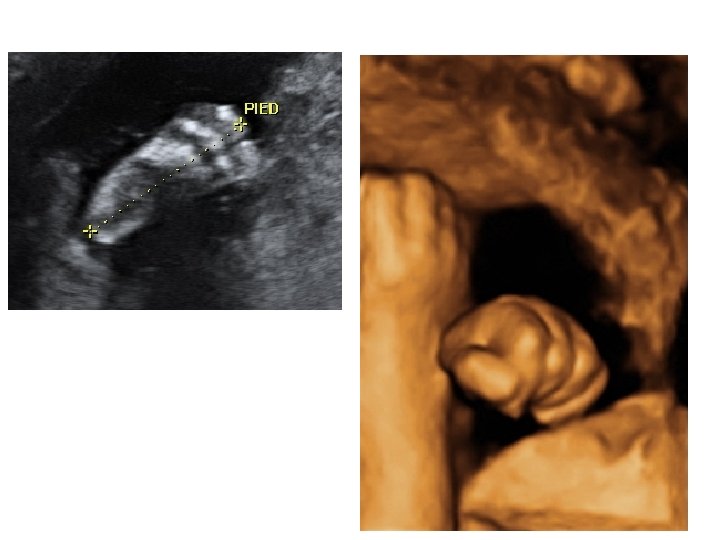

- thorax : cœur (position, 4 cavités équilibrées, septum inter ventriculaire, croisement Ao/AP), poumons - abdomen : paroi intègre, estomac (position, volume), vésicule biliaire, intestin grêle - arbre urinaire : vessie (position, volume), 2 reins - sexe - rachis avec son revêtement cutané - membres : 4 x 3 segments, 5 doigts aux 2 mains, mouvements d’ouverture des mains, mesure du pied

• Étudier les annexes fœtales - cordon: 2 artères, 1 veine - placenta : épaisseur et niveau d’insertion - liquide amniotique : volume.